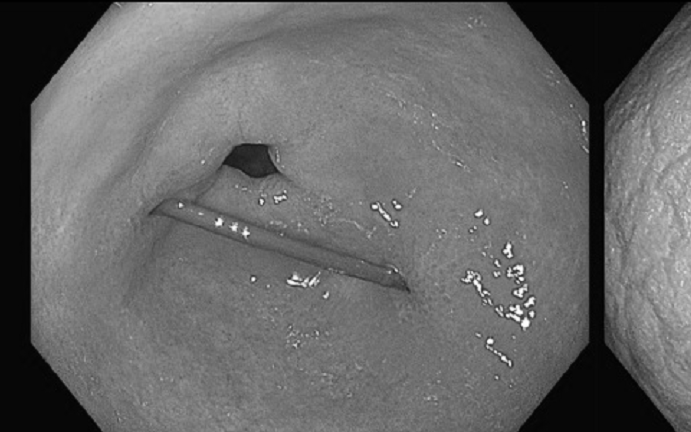

Thông tin ban đầu bé nhập viện trong tình trạng đau bụng, người nhà thấy con thường hay ăn tóc... Qua siêu âm và thăm khám, bác sĩ phát hiện dạ dày bệnh nhi chứa đầy dị vật dạng tóc. Trẻ được chỉ định nội soi tiêu hóa gây mê, kết quả búi tóc chiếm toàn bộ dạ dày.

Ngay sau khi hội chẩn, ê-kíp phẫu thuật đã tiến hành mở dạ dày lấy dị vật. Các bác sĩ gắp ra một búi tóc rất lớn, xoắn chặt, chiếm toàn bộ dạ dày của bệnh nhi, cân nặng khoảng 0,5kg.